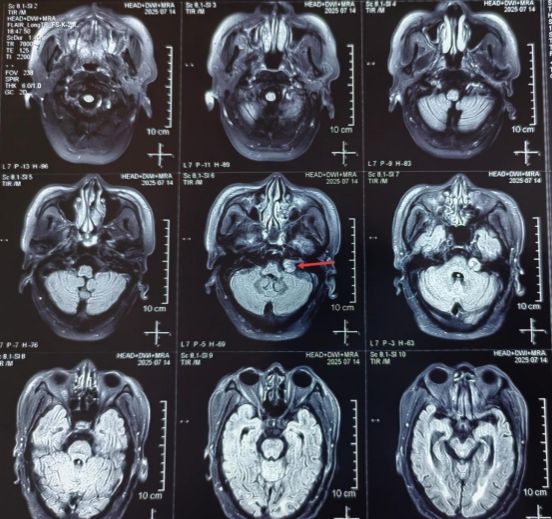

2025-09-30除病灶,保功能!我院神经外科二病区郭清保主任团队成功切除桥小脑角区占位性病变

68岁李大爷(化名),平时有高血压、脑萎缩、腔隙性脑梗死、冠心病等慢性病史,6年前还有过脑出血。近期,因较长时间的走路不稳、耳鸣,多次摔倒,家属陪伴至医院就诊。... -